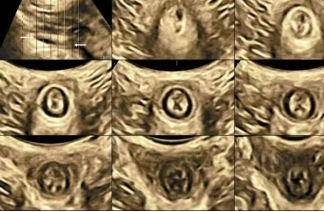

您是否也遇到过这些尴尬时刻?提重物时突然漏尿、运动时总觉下腹坠胀、更年期后总想跑厕所......这些信号可能在提醒:盆底肌需要关爱了。 盆底肌群如同"弹簧床",承托着膀胱、子宫等器官。妊娠分娩、雌激素变化、长期腹压增加等因素,都可能导致这张"网"松弛。若不及时干预,可能发展为: ▷ 盆腔器官脱垂(子宫/阴道膨出) ▷ 压力性尿失禁(咳嗽/大笑漏尿) ▷ 排便障碍(便秘/失禁) ▷ 性生活质量下降 【哪些人需要关注盆底筛查?】 ✓ 产后42天妈妈(尤其经阴道分娩) ✓ 频繁漏尿或排尿困难 ✓ 长期便秘/慢性咳嗽 ✓ 更年期女性 ✓ 性生活疼痛或下腹坠胀人群 【无创筛查新选择:盆底超声】 不同于传统指检,这项技术通过会阴体表扫描: ⏩ 多维度观察静息/收缩/用力状态 ⏩ 精准评估肌群损伤程度 ⏩ 动态捕捉器官位移情况 女性盆底三维多层显像 【检查须知】 ✔️ 避开经期 ✔️ 检查前排空膀胱 ✔️ 穿宽松裤装更方便 ✔️ 配合医生指令做缩肛/屏气动作 盆底超声检查 女性健康管理不该止于体检常规项。建议存在相关症状的女性,及时到正规医院妇产科或超声科咨询。早筛查、早干预,让盆底肌恢复应有的"托举力"。 注:部分图片来源于网络,如有侵权,请联系删除。 贵州航天医院超声科专家团队 吴艳辉 中共党员,超声科学科带头人、主任,主任医师 专业擅长:从事超声诊断工作约30年,对心血管、小器官超声、超声引导下介入等具有丰富的临床经验。 胡大海 超声科副主任,副主任医师 专业擅长:从事超声工作17年,对心血管、外周血管、浅表器官超声诊断等具有丰富的临床经验。 骆科美 中共党员,超声科副主任医师 专业擅长:从事超声诊断工作33年,对胎儿心脏及颅脑、妇产超声诊断、盆底超声等诊断具有丰富的临床经验。 刘 敏 超声科副主任医师 专业擅长:从事超声诊断工作20余年,对妇产科超声、心脏血管超声诊断具有丰富的临床经验。 贵州航天医院超声科简介 基本情况 贵州航天医院超声科配备多种超声检查设备(飞利浦彩超(IU-22、IU-Elite、HD11、Q5、Q7),迈瑞超声I9、DC-6、DC-8、GE-E8及床旁机,彩色超声诊断仪等),设有心血管诊室、妇产科诊室、腹部诊室、绿色通道、浅表小器官等检查室。 诊疗范围 科室业务覆盖腹部、泌尿、妇科、产科(常规、NT筛查、III级筛查超声检查及高危妊娠监护)、成人心脏、外周血管、浅表器官(包含甲状腺、乳腺、阴囊、眼睛等)、颅脑(小儿颅脑、成人颅脑)、小儿肺超、造影、盆底、腹直肌、肌骨神经等检查及各种介入引导。 专科特色 四肢血管超声检查、双胎产前筛查及超声监护、超声造影检查技术、介入超声临床应用、经颅脑实质超声辅助筛查诊断帕金森病、女性性早熟超声诊断、盆底超声检查等。 NT超声检查 超声介入引导 肝脏超声造影 甲状腺造影 颅脑超声帕金森辅助检查 乳腺超声造影 上肢动静脉造瘘超声检查 双胎超声筛查 下肢血管超声检查 右心造影 END